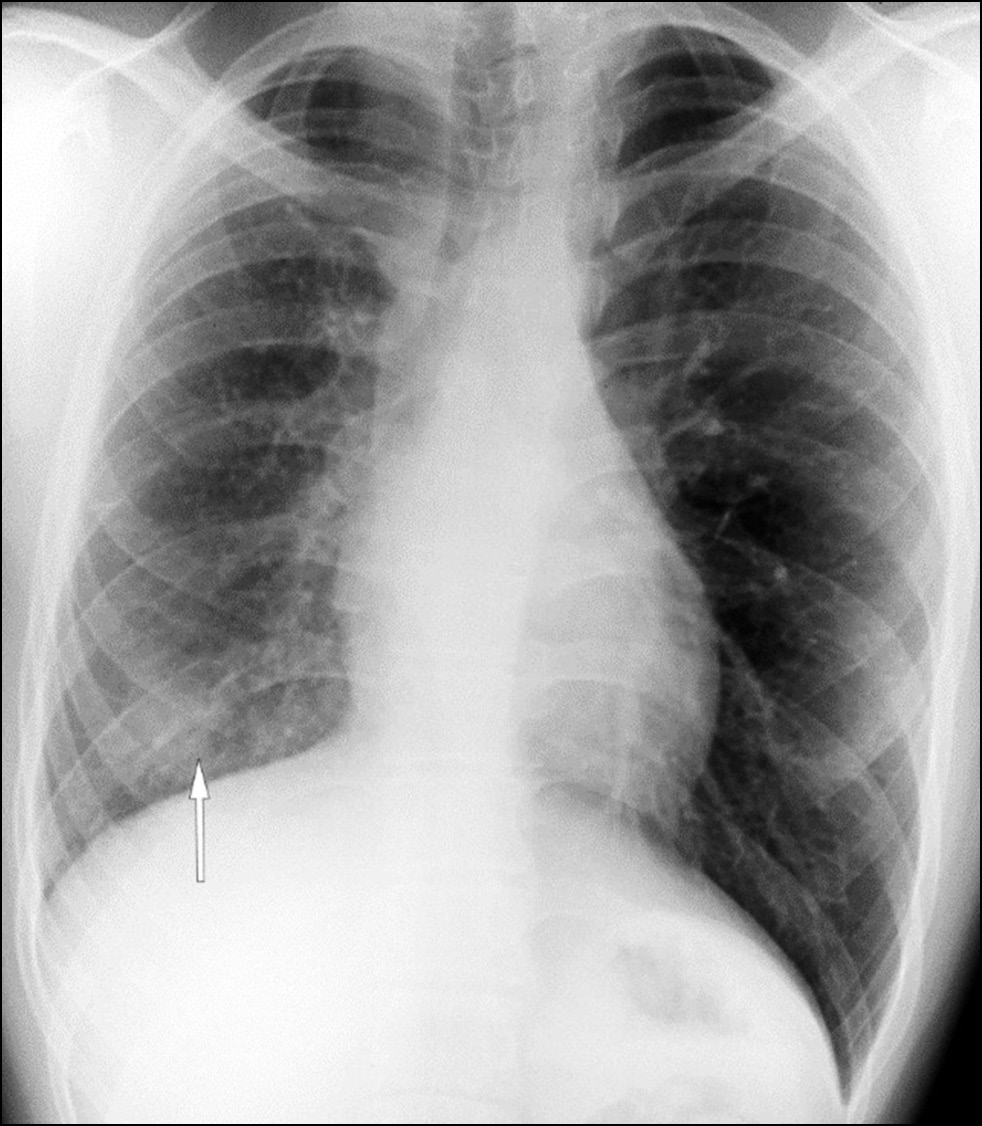

Pulmonary vein atresia is a rare congenital abnormality that could manifest in isolation or in association with other congenital abnormalities in the cardiovascular system such as pulmonary vein hypoplasia. Pulmonary vein atresia leads to changes in cardiovascular functioning. This abnormality is often diagnosed in children with recurrent pneumonia and hemoptysis. In adulthood, pulmonary vein atresia is much less common, with clinical symptoms such as dyspnea during physical exercises and hemoptysis. However, some patients are asymptomatic. Owing to the nonspecific imaging findings, lung parenchymal changes are often misdiagnosed as another lung disease, including inflammatory genesis disease. In this article, a case of a young man with asymptomatic unilateral pulmonary vein atresia combined with pulmonary artery hypoplasia and interstitial lung changes in a lung with hypoplasia was presented. These pathologies were first identified in a 21-year-old patient by contrast-enhanced computed tomography.